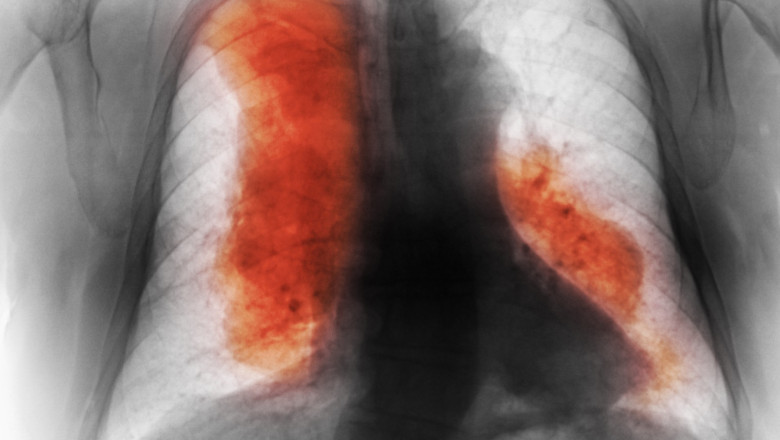

Majoritatea pacienţilor trăiau în ţări cu venituri mici şi medii. Cancerul mamar a fost cel mai frecvent diagnosticat tip de cancer în 2023. Însă, cancerele traheale, bronhice şi pulmonare reprezintă cele mai frecvente cauze de deces.